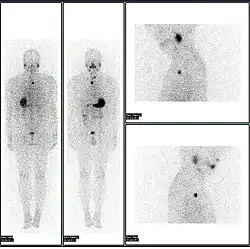

A nuclear medicine PET scan

Nuclear medicine (nuclear radiology)[1] is a medical specialty involving the application of radioactive substances in the diagnosis and treatment of disease. Nuclear imaging is, in a sense, radiology done inside out, because it records radiation emitted from within the body rather than radiation that is transmitted through the body from external sources like X-ray generators. In addition, nuclear medicine scans differ from radiology, as the emphasis is not on imaging anatomy, but on the function. For such reason, it is called a physiological imaging modality. Single photon emission computed tomography (SPECT) and positron emission tomography (PET) scans are the two most common imaging modalities in nuclear medicine.[2]